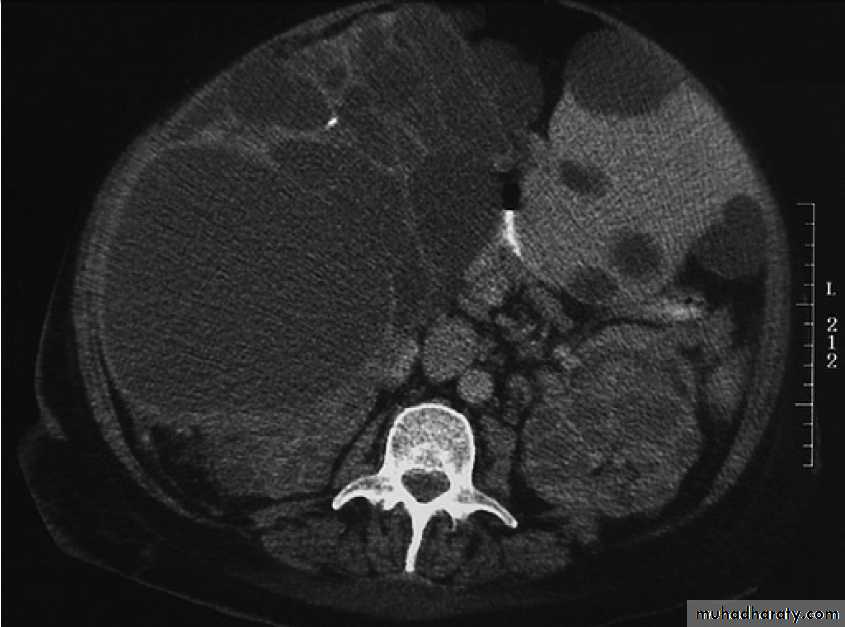

Hydatid cyst of the liver on CT (arrows).